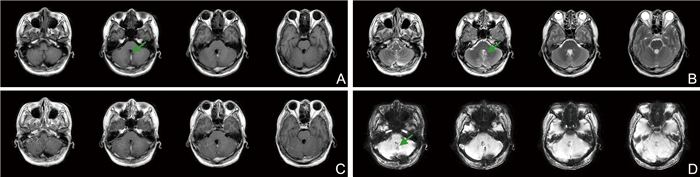

Analysis of the diagnostic efficacy of digital breast tomosynthesis in patients with early-stage breast cancer

YANG Yan, ZHAO Yunian, MAO Changfei, TANG Xiaowen, LI Dongxue

2025, 23(6): 1004-1007. doi: 10.16766/j.cnki.issn.1674-4152.004053

67 3

Abstract:

Objective  To investigate the diagnostic efficacy of digital breast tomosynthesis (DBT) in detecting early-stage breast cancer and compare its efficacy with that of magnetic resonance imaging (MRI).  Methods  A retrospective analysis was conducted on 50 patients diagnosed with early-stage breast cancer between January 2023 and December 2023. All patients underwent imaging examination, with complete and high-quality imaging data prior to pathological examination. The pathological findings were used as the gold standard to compare detection accuracy, sensitivity, and specificity DBT and MRI, as well as breast cancer staging consistency between imaging and pathology.  Results  The rates of missed diagnoses, misdiagnosis, and accuracy in detecting breast lesions for DBT were 4.00% (2/50), 6.00% (3/50), and 90.00% (45/50), respectively. Compared with MRI [2.00% (1/50), 4.00% (2/50), and 94.00% (47/50)], these differences were not statistically significant. Based on the pathological examination results as the gold standard, there was no statistically significant difference in the diagnostic results of DBT for breast cancer type classification. A total of 87 breast masses (54 malignant and 33 benign) were identified in 50 patients with early-stage breast cancer. DBT demonstrated lower diagnostic sensitivity and negative predictive value than MRI, it exhibited higher specificity and positive predictive value. Overall diagnostic accuracy was comparable between the two modalities. The cost-benefit ratio (CER) for DBT and MRI were 3.25 and 12.17, respectively, and the incremental cost-benefit ratio (ICER) for MRI relative to DBT was 713.91.  Conclusion  Digital breast tomosynthesis offers high accuracy and favorable cost-effectiveness in the diagnosis of patients with breast cancer, making it a valuable tool worthy of broader clinical application.